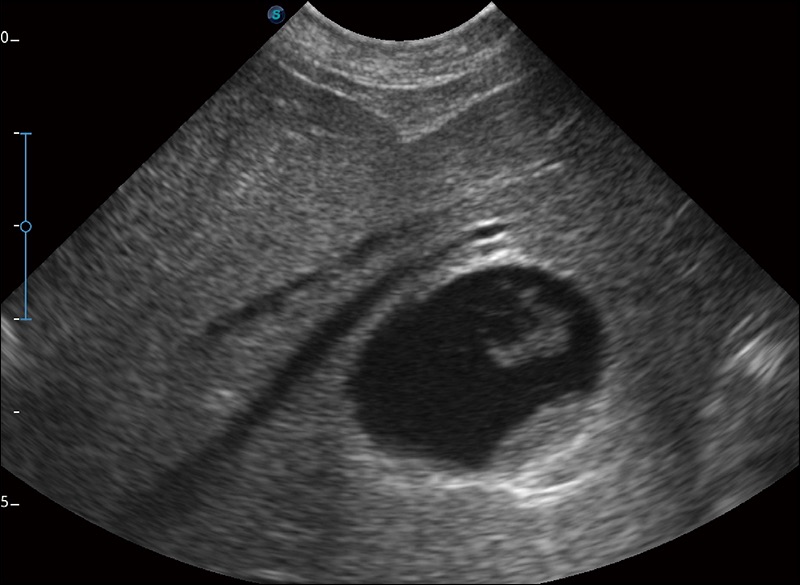

穿刺针增强

高清显示穿刺进针情况